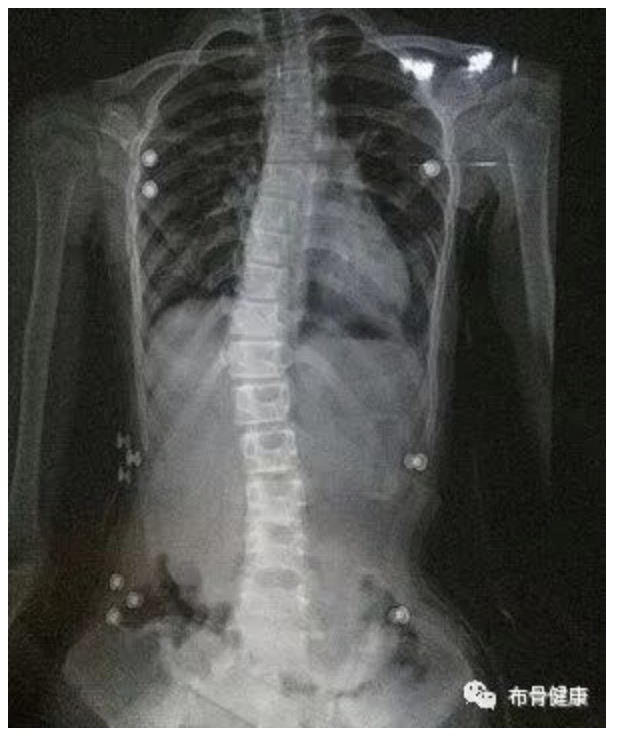

记得小时候,父母和老师总是喜欢拍拍自己的后背说到:“坐直了,小心长大了变成大锣锅”。长大后才发现,有一种疾病,比坐姿问题更加可怕。它就是脊柱侧弯。

多数家长都认为孩子驼背、肩膀不平等问题一定是坐姿不正确引起的,因此往往在日复一日的唠叨中忽视了孩子脊柱侧弯的可能性,当真正发现时,孩子已经过了生长发育的高峰期,脊柱侧弯也进展到了较严重的程度。

脊椎侧弯对健康的影响,除了体态外观上的问题外,多半会引起长期的腰背酸痛,另外脊椎关节在长期受力不均之下,可能发生退行性关节炎;如果侧弯持续增大,可影响心肺功能;非常严重的畸形也可能会压迫神经根和脊髓,引起瘫痪。

对于脊柱侧弯,早期发现非常重要,家长有助于早期发现,那么,如何能早期发现孩子患有脊柱侧弯呢?